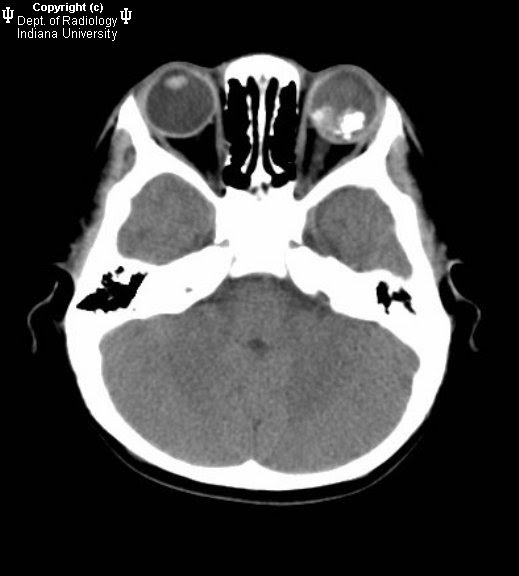

Neuroradiology On the Net Retinoblastoma Retinoblastoma Benign Or Malignant Retinoblastoma is the most common primary intraocular malignancy of childhood and accounts for 10 to 15 percent of. Retinoblastoma is a malignant tumor of the developing retina that occurs in children, usually before age. And when it does happen, the overall odds of a good outcome are high, especially with early. 90% of all retinoblastoma cases are diagnosed by 3.. Retinoblastoma Benign Or Malignant.